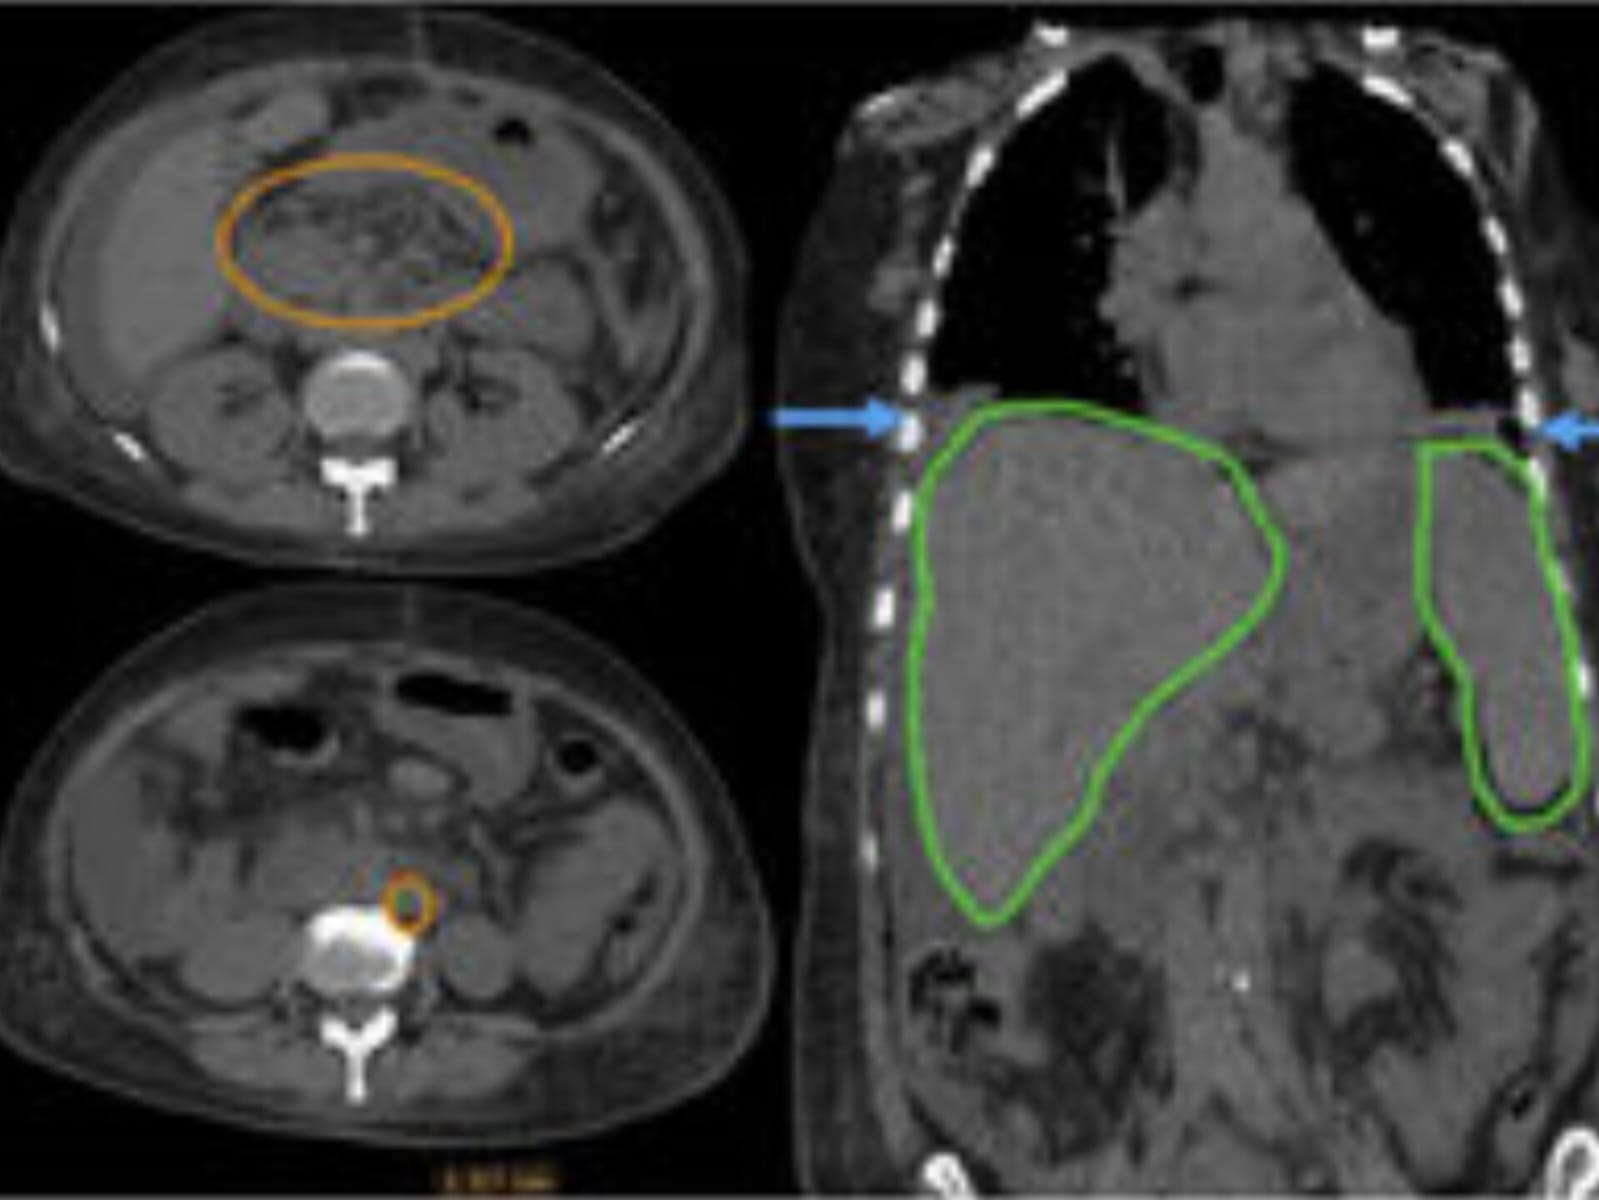

Na maioria das vezes, a doença começa nos pulmões, mas pode se espalhar para outros órgãos, como pele, mucosas, linfonodos e até o sistema nervoso central.